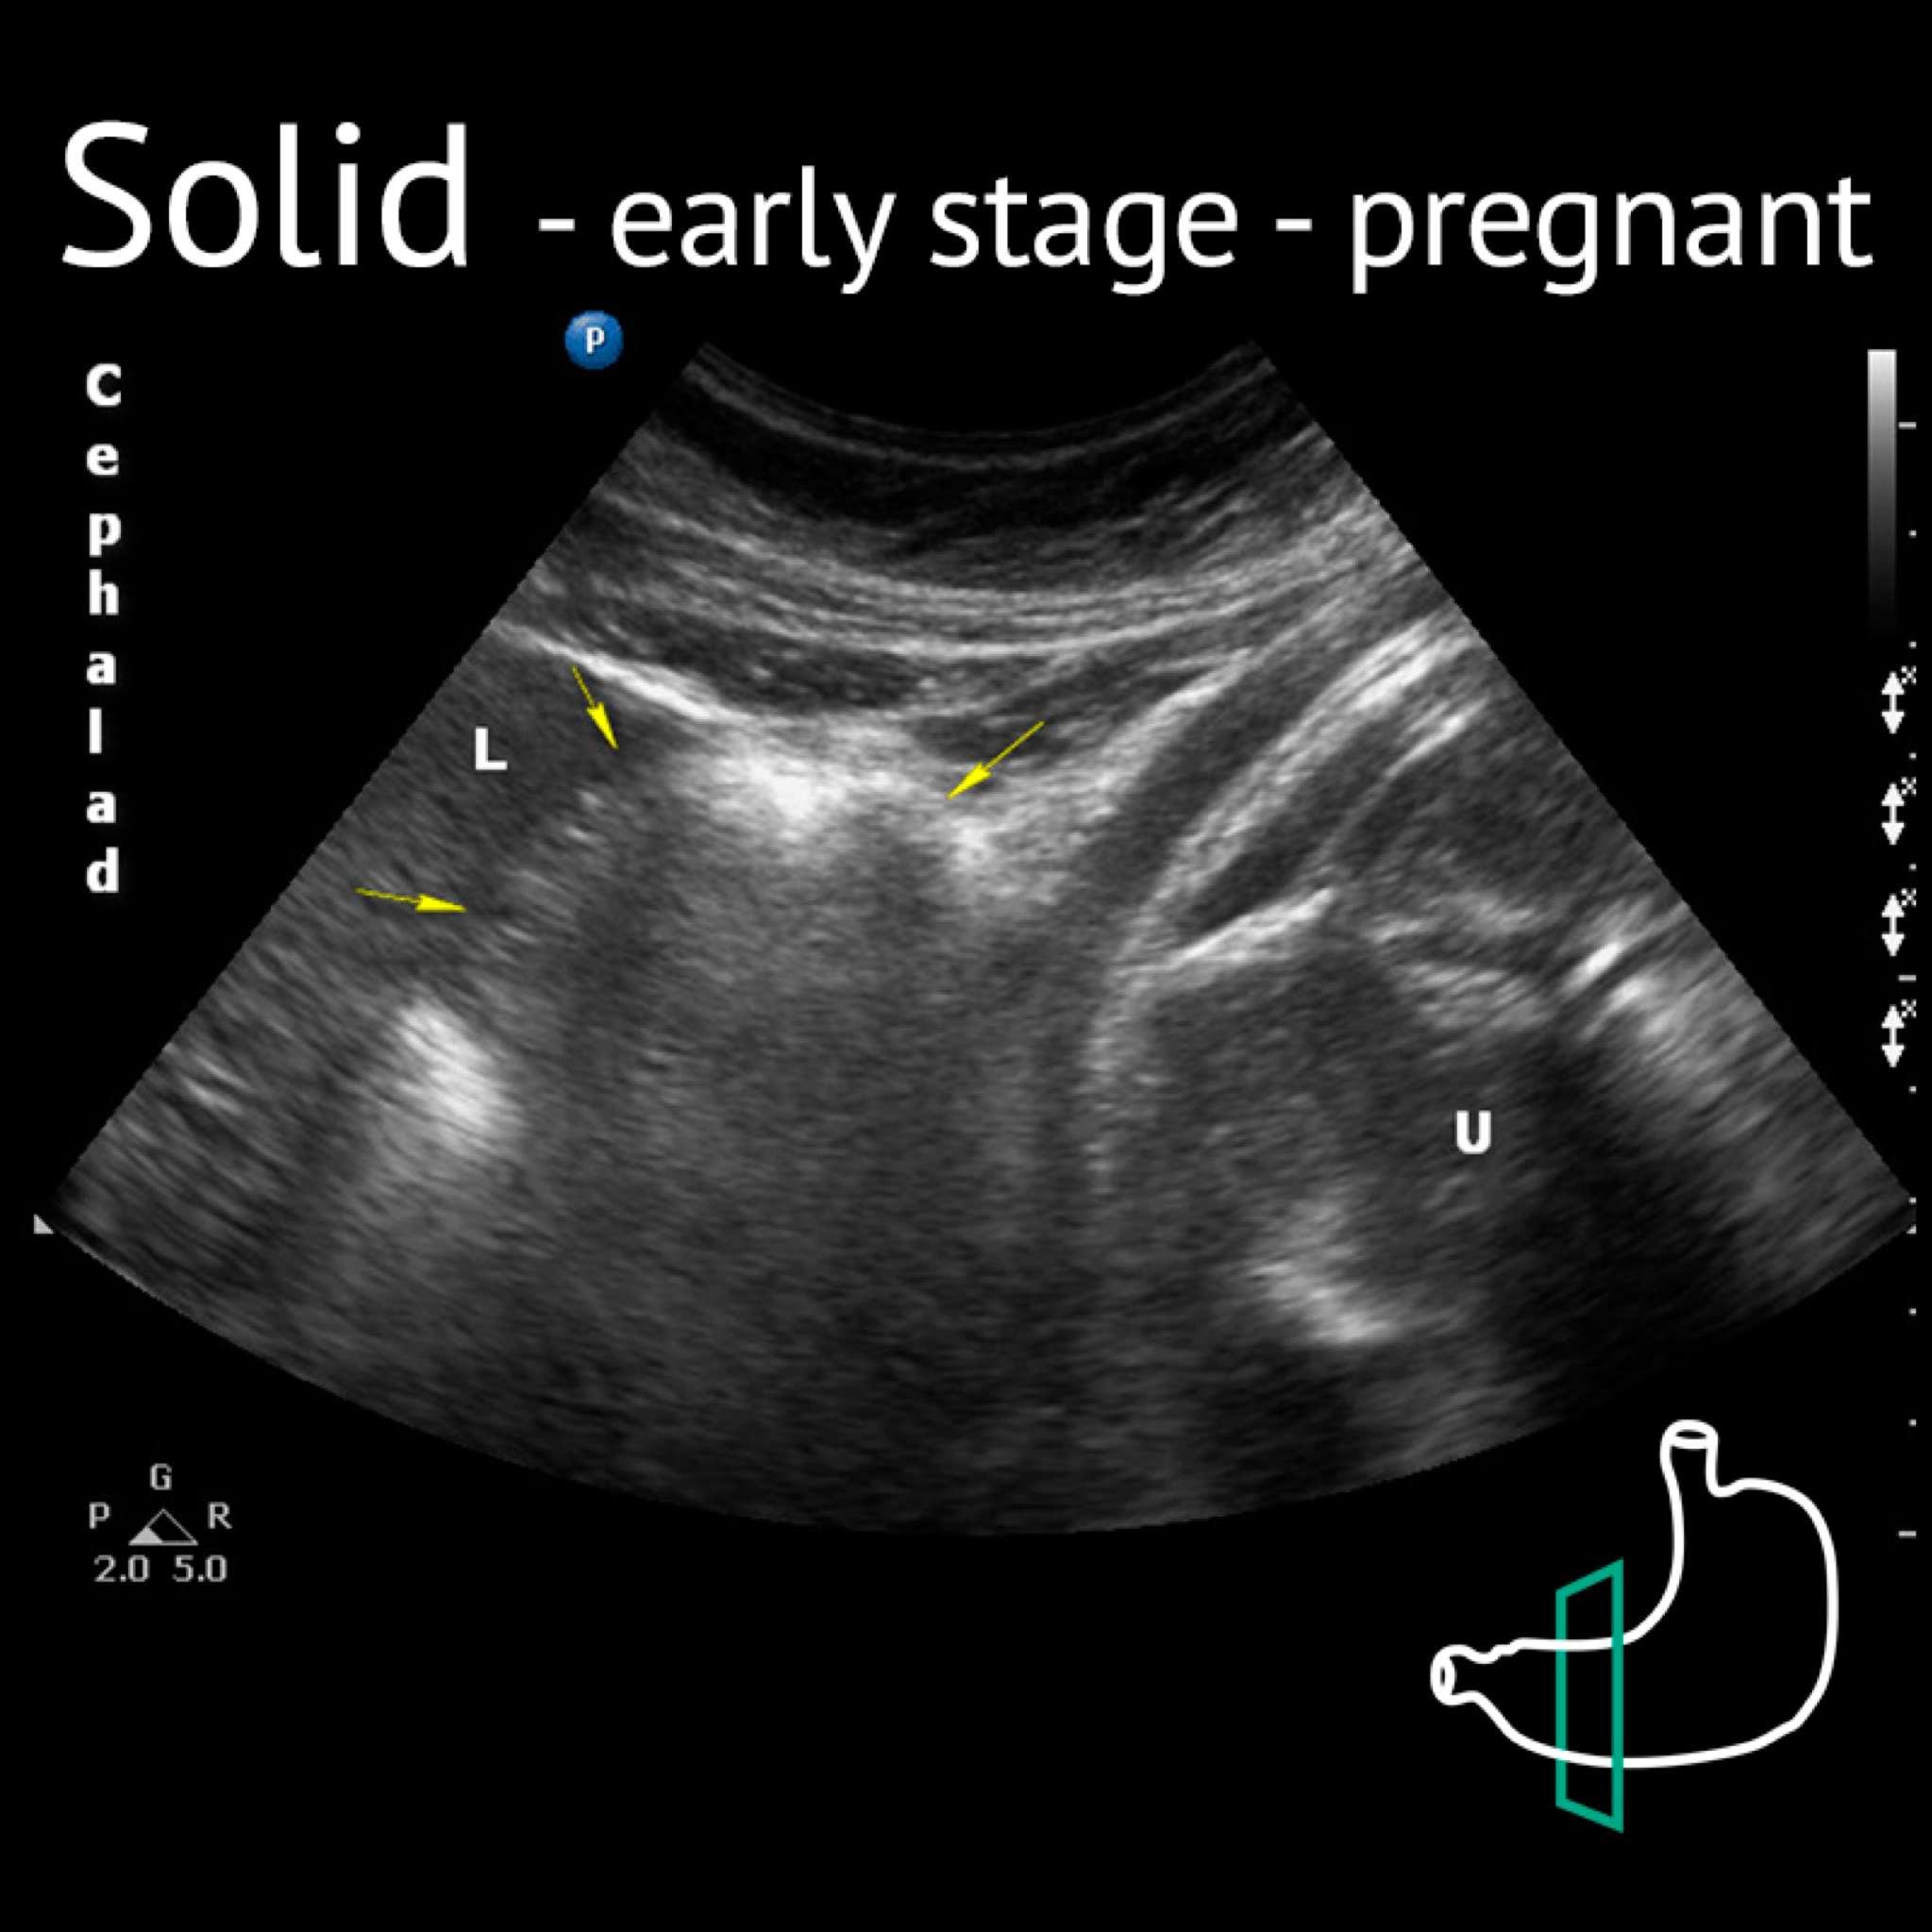

L: liver; U: uterus; Yellow arrows: antrum